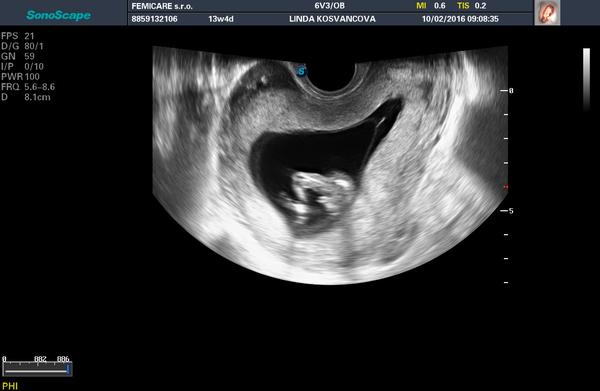

Vidíte holčičku nebo chlapečka?

Jsem ve 14tt a na posledním ultrazvuku mi pan doktor řekl, že asi vidí chlapečka. Ale je to 50/50 a ruku do ohně za to nedá. Zajímalo by mě, co vidíte vy? Jen tak pro zajímavost 🙂

Myslím si že chlapeček...holčička má jakoby švestku 😀

Za mě taky chlapeček 🙂

ta fotka se mi nechce zobrazit, ale takhle brzo se to poznává podle pohlavního hrbolku